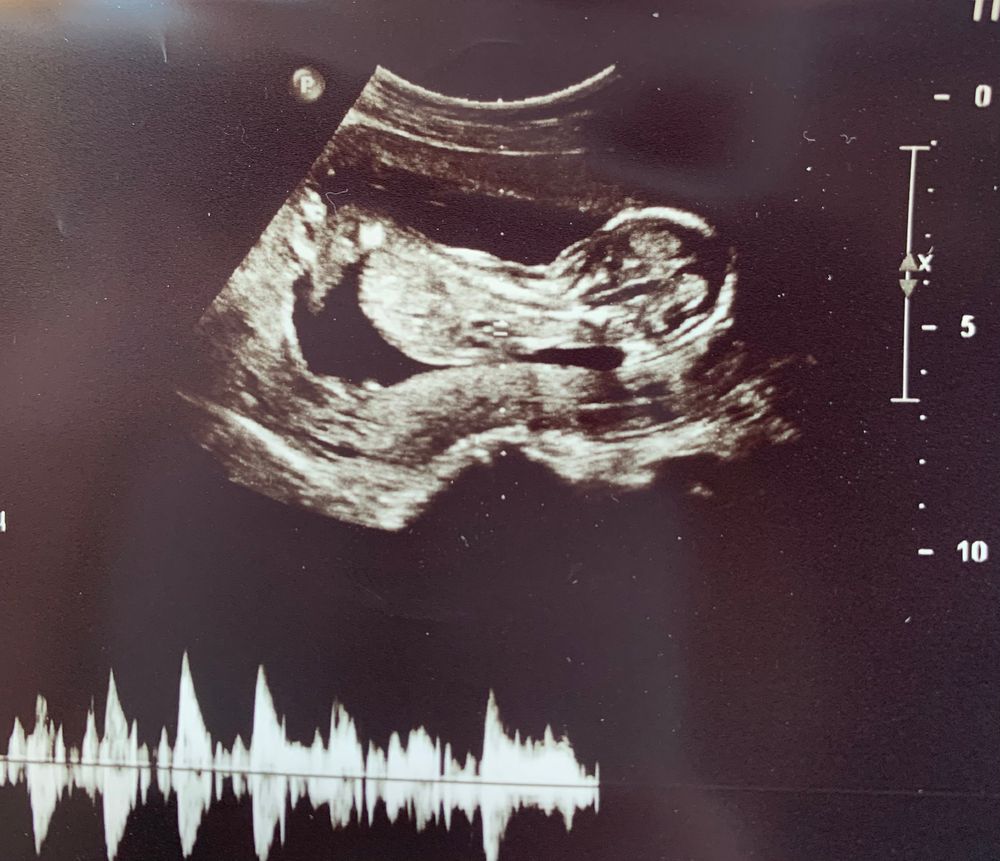

Всем привет! У меня ещё один не очень информативный снимок 🙈 сегодня ровно 15 недель. Узи было другого органа, малыша глянули на минутку , ножки опять скрестил и все спрятал. Снимок только такой. Может кто-нибудь сможет предположить кто же там прячется? После двух мальчиков сгораю от любопытства кто же третий, на второй скрининг через недели три только

Вот так по-турецки сидит больше месяца😀